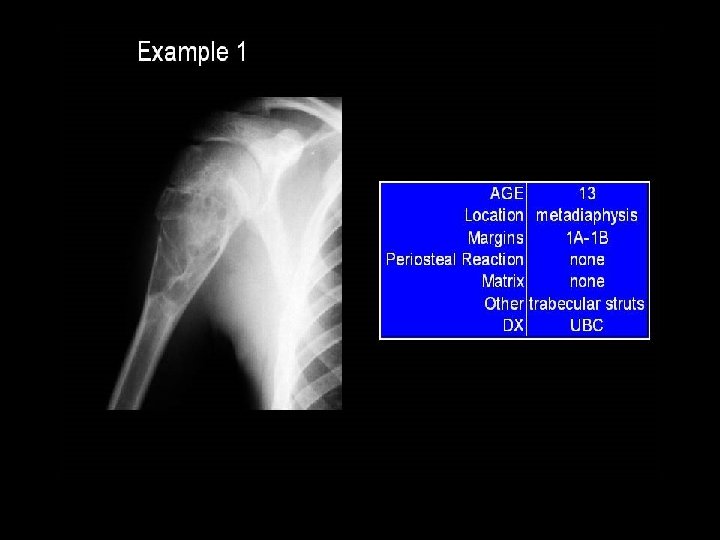

Simple bone cyst • Unicameral bone cyst • Metaphysis of long bones (humerus , femur) • Centric • Filled with straw-coloured fluid

• Bone Cyst – A wall of fibrous tissue filled with clear fluid • Clinical presentation • Pain • Not diagnosed unless a pathological fracture occurs.

Bone Cysts simple bone cyst l fibrous dysplasia l aneurysmal bone cyst l